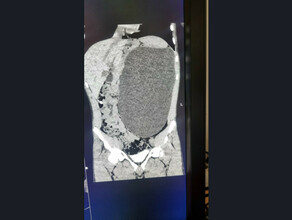

Фото: демонстрационное фото

Подросток из Москвы чуть не лишился почки из-за того, что в течение двух месяцев не мог сходить в туалет. Об этом сообщает Telegram-канал Baza.

По данным источника, 15-летний Максим обратился к врачам из-за проблем с почками. Для исправления патологии ему была проведена операция, в ходе которой мочеточник соединили с мочевым пузырем. Спустя месяц после хирургического вмешательства медики удалили трубку для отвода мочи, однако через два часа после этого у молодого человека началась сильная боль в боку и повысилось давление, пишет канал.

«Выяснилось, что почка раздулась из-за того, что из нее не может выйти моча. По словам матери ребенка, врачи не стали как-либо исправлять ситуацию и отправили подростка домой, отметив, что такое случается после операций», – пишет Lenta.ru.

Через два месяца после этого молодой человек был снова госпитализирован из-за «невыносимой боли». Оказалось, что прооперированный мочеточник полностью зарос, и все это время почка не могла выводить отходы. Тогда врачи вывели трубку через прокол в спине.